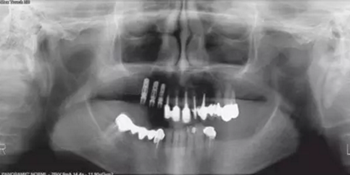

#13~16:拔除#13~15后種植修復(fù)(Straumann骨組織水平RC種植體,Roxolid材料,SLActive表面)?;颊邔⒂幸粋€(gè)較短的牙弓。然而,咬合力可以被平均分配并且咀嚼效率不會(huì)受到明顯影響。目前的狀況迫使我們妥協(xié),在右上尖牙、前磨牙和磨牙的位置放置3顆植體(圖2)。

圖2

我們的目標(biāo)是無(wú)創(chuàng)拔除這3顆齲壞牙齒,不翻瓣即刻植入種植體并即刻負(fù)載從而可以修復(fù)其他區(qū)段牙齒。為了最大限度的保證準(zhǔn)確性并減少步驟,我們使用了數(shù)字化手術(shù)導(dǎo)板,這樣術(shù)后可以完成螺絲固位的CAD/CAM臨時(shí)修復(fù)。